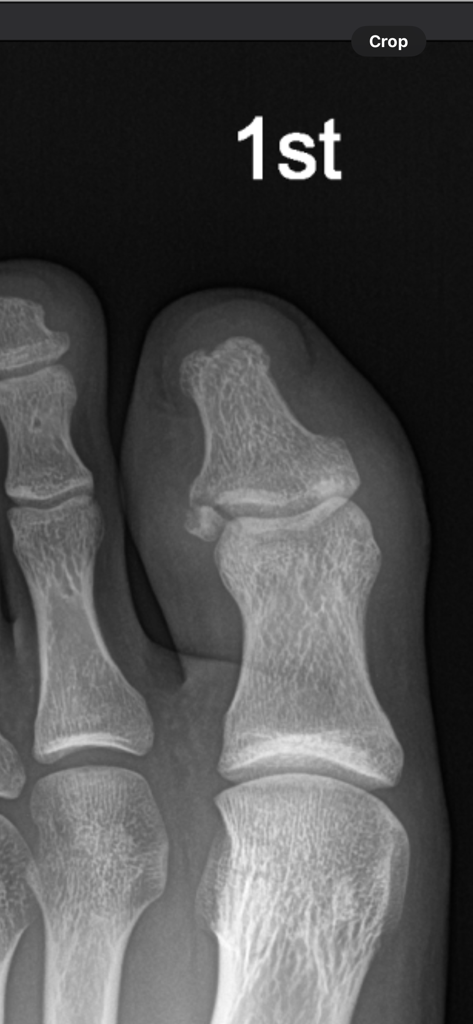

좌측 원위지골 골절 후 전위가 발생했는게 저정도 뼈조각과 저정도 전위는 핀으로 고정 하기 어려운가요? 수술은 필요 없어보이나요?? 현재 전위 정도와 뼈조각 위치를 어떻게 보시나요??

참고로 골절된지 15일 후 사진입니다.

• 1번 째 사진

크기도 작고 위치도 참 애매한 부위입니다.

그대로 지켜보는것도 한가지 방법이 될수 있겠습니다.